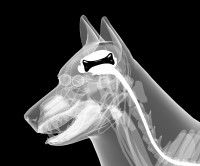

La moelle épinière, aussi appelée moelle spinale, appartient au système nerveux central et se situe dans le prolongement de l'encéphale, et plus particulièrement du tronc cérébral. Elle est située à l'intérieur de la colonne vertébrale du chien, qui la soutient et la protège des agressions et des chocs.

Le rôle de la moelle épinière est d'assurer la transmission d'informations entre le cerveau et le reste du corps. Elle est constituée de 3 circuits principaux : un qui transmet les ordres moteurs vers les muscles, un qui relaie les informations sensorielles jusqu'au tronc cérébral, et un qui gère certains réflexes.

Elle est le point de départ de nerfs dits spinaux, par opposition aux nerfs cérébraux (qui partent du cerveau). Il existe 36 paires de nerfs spinaux chez le chien, alors qu'il n'y en a que 31 chez l'Homme. Chacun se subdivise ensuite en un grand nombre de nerfs périphériques afin de se propager dans l'ensemble de l'organisme.

Lorsque la moelle épinière est endommagée, que ce soit du fait d'un choc violent, d'une malformation ou d'une maladie (la spina bifida par exemple), la transmission des informations vers l'ensemble du corps est altérée voire interrompue. Selon la localisation et la gravité de l'atteinte, il peut donc en résulter une paralysie des membres postérieurs voire des quatre membres, une incontinence urinaire et/ou fécale, des problèmes de coordination des membres, etc.